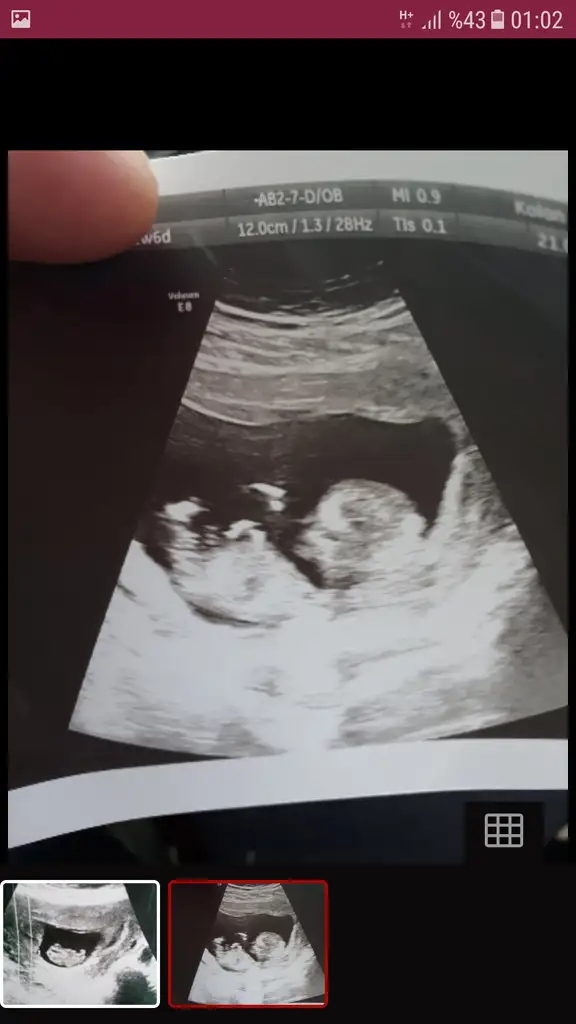

Kizlar cinsiyet tahmininiz varmi dr 12 hafta kiza benzetti 13 hafta baska dr yuzde 55 kiz gibi ama tam goremedim dedi ruyamda oglum olursa adini hamza yilmaz koyucam diyorum hep erkek hissettim ama kizada alistim hayirli saglikli olsun en basta tabiki cuma gunu kontrolum var dr kesinlesir dedi sizin tahminlerinizide alabikirmiyim ilk ikisi 12+digeri 13 haftalik

Eklentiler

• Screenshot_20190630-010258.webp

Screenshot_20190630-010258.webp

17,9 KB · Görüntüleme: 191

• Screenshot_20190704-182556_Samsung Internet.webp

Screenshot_20190704-182556_Samsung Internet.webp

27,1 KB · Görüntüleme: 197

• Screenshot_20190628-223445.webp

Screenshot_20190628-223445.webp

28,8 KB · Görüntüleme: 171